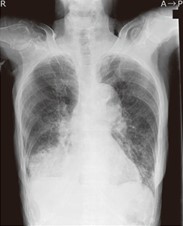

A胸部X腺写真

誤嚥が明らかな場合や嚥下機能低下が確認されいる患者で撮影します。

胸部エックス線写真で肺炎像を確認することで診断できます。